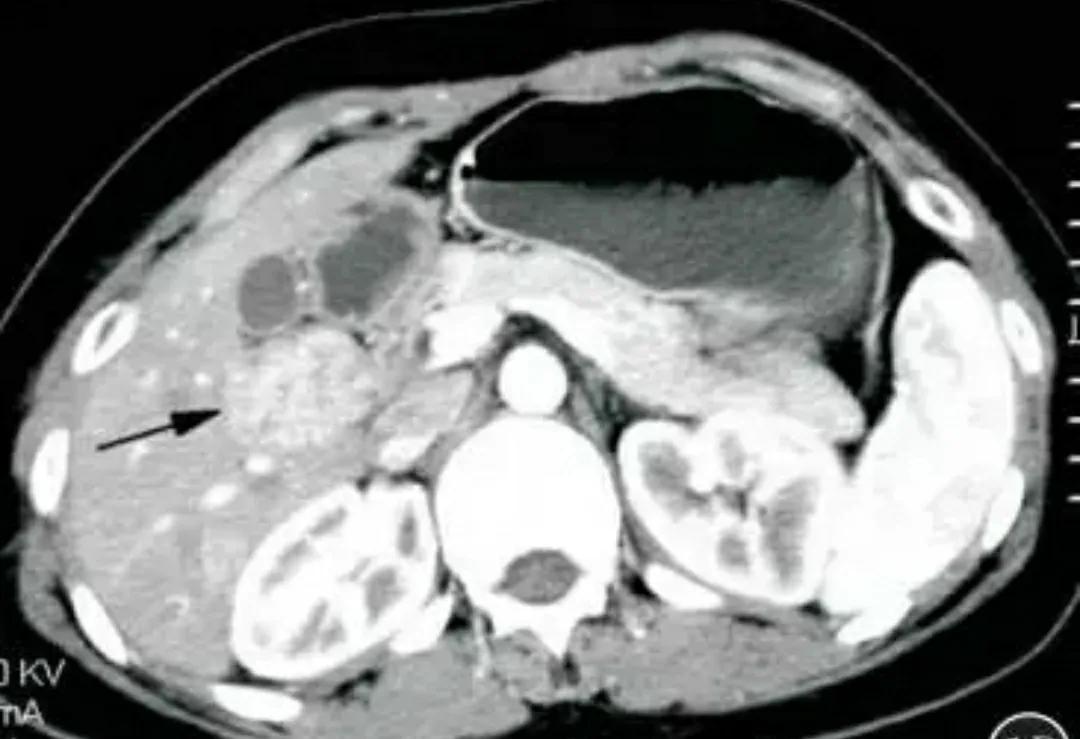

超声所见:直径<3cm的肝癌结节常常包膜完整,癌结节内部回声高低不一,且具多变倾向,癌结节可有低回声结节、高回声结节、混合性结节,还可以是等回声结节。肝癌结节及其周围血供丰富,彩色多普勒超声能准确反映肝癌的血供情况。

肝癌超声声像图